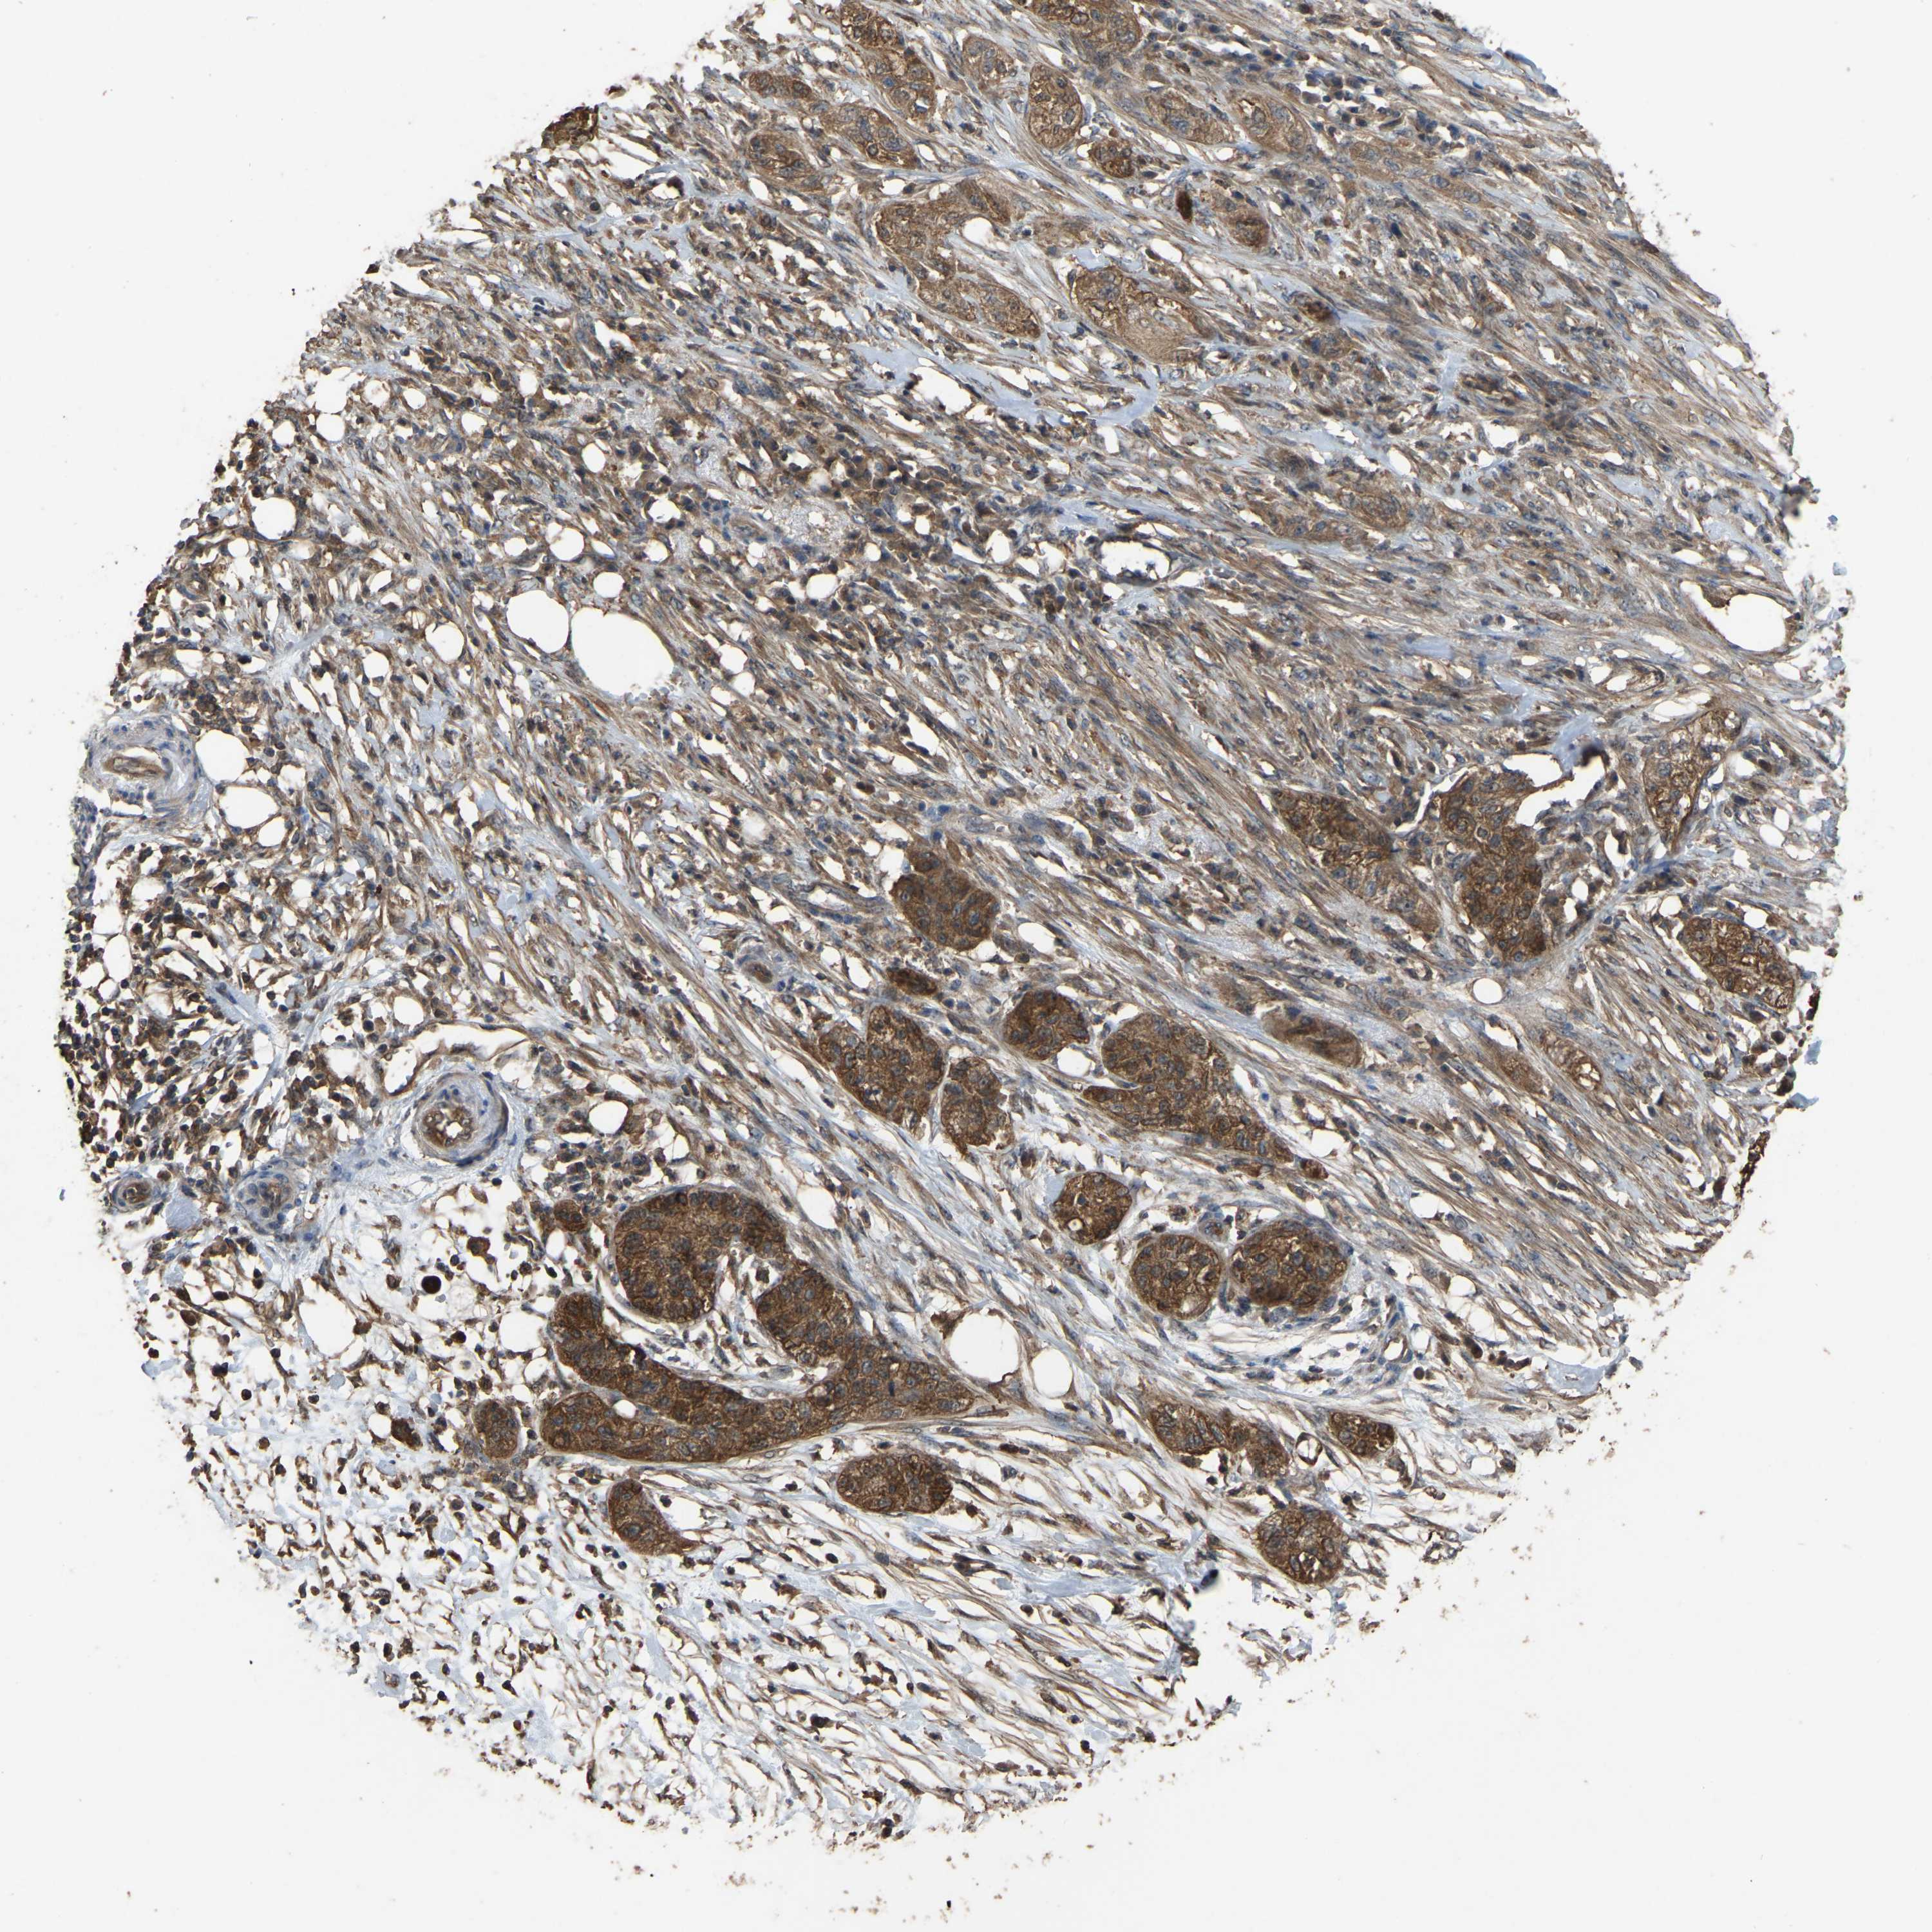

PANCREATIC CANCER - Protein expressioni

A mouse-over function shows sample information and annotation data. Click on an image to view it in a full screen mode. Samples can be filtered based on level of antibody staining by selecting one or several of the following categories: high, medium, low and not detected. The assay and annotation is described here.

Note that samples used for immunohistochemistry by the Human Protein Atlas do not correspond to samples in the TCGA dataset.

Antibody stainingi

Antibody staining in the annotated cell types in the current human tissue is reported as not detected, low, medium, or high, based on conventional immunohistochemistry profiling in selected tissues. This score is based on the combination of the staining intensity and fraction of stained cells.

Each image is clickable and will lead to virtual microscopy that enables deeper exploration of all samples and also displays staining intensity scores, fraction scores and subcellular localization as well as patient and tissue information for each sample.

Antibody HPA018840

Antibody HPA018909

Antibody CAB002684

Staining

High

Medium

Low

Not detected

Intensity

Strong

Moderate

Weak

Negative

Quantity

>75%

75%-25%

<25%

None

Location

Nuclear

Cytoplasmic/membranous

Cytoplasmic/membranous,nuclear

Adenocarcinoma, NOS

Adenocarcinoma, metastatic, NOS